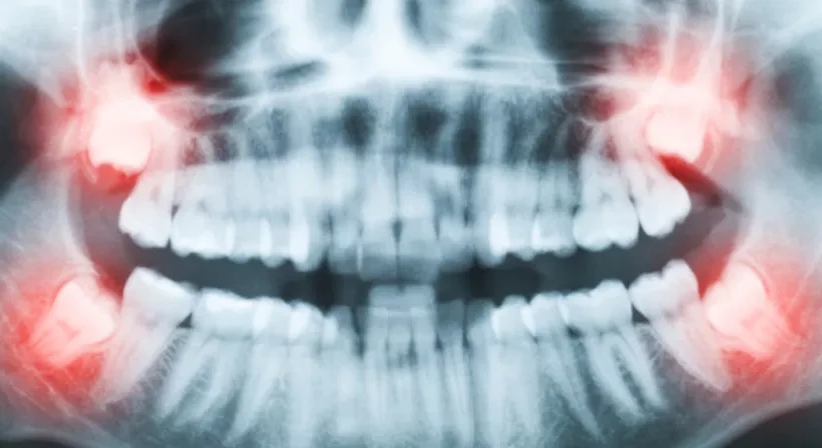

Von der Mitte aus gezählt ist der Weisheitszahn der achte Zahn im menschlichen Gebiss. Im Regelfall befindet sich in jedem Quadranten ein Weisheitszahn. Da sich im Laufe der Zeit das Gebiss des Menschen verkürzt hat, findet der Weisheitszahn bei vielen Menschen beim Durchbrechen nicht mehr ausreichend Platz. In weiterer Folge kann es zu Entzündungen, Abszessen, starken Schmerzen sowie zu einer behinderten Kaufunktion und Kiefergelenksbeschwerden kommen.